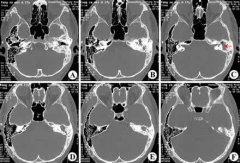

胆脂瘤型中耳乳突炎必须做手术吗 治疗案例

患者自幼双耳廓畸形,与人交谈困难。2年前出现左耳流黄色脓性分泌物并反复发作,分泌物有异味。伴有耳痛,呈持续性胀痛。半月前左耳后皮肤红肿,瘘口处有脓液。近一个月来患者自觉右耳听力比以前有下降。... [详情] 文章日期 :17-07-05